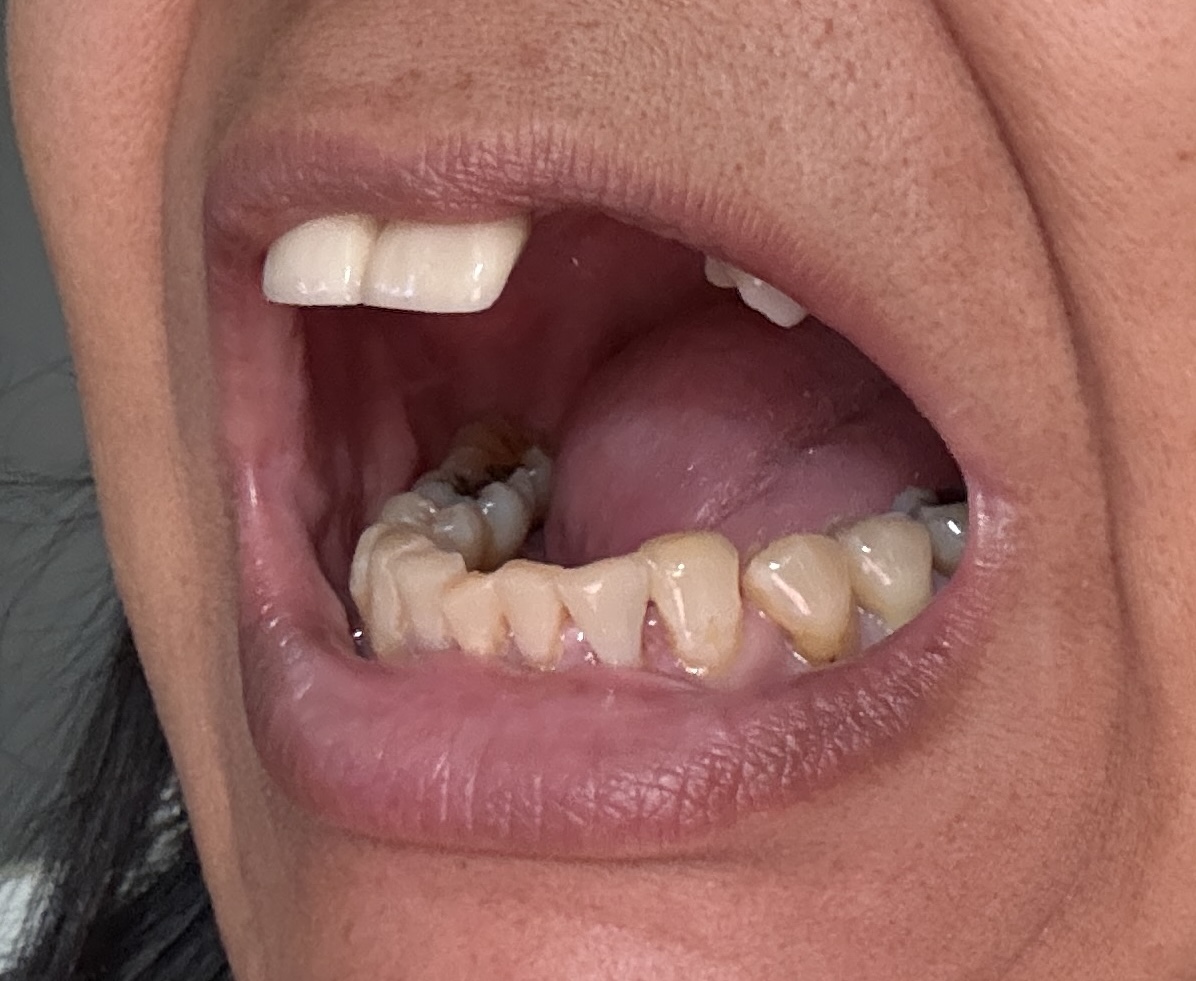

12,13,14 have had root canals in past and now have quite a bit movement. 2-5 have all had root canals in past and now the crowns are breaking down.

Overall information (lower arch)

Overall, all of my gums have receded and most of the bottom teeth are exposed w/ some roots and there are many cavities.